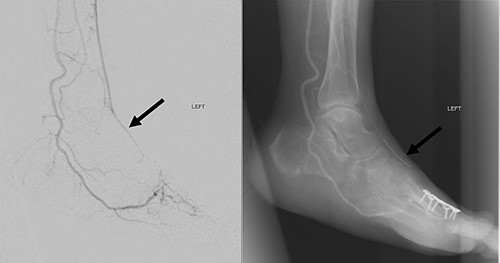

Left lower limb diagnostic angiogram showing occlusion of the ATA with poor flow (arrow).

Angiogram of left distal leg and foot showing poor flow of the distal ATA and dorsalis pedis artery (arrow).